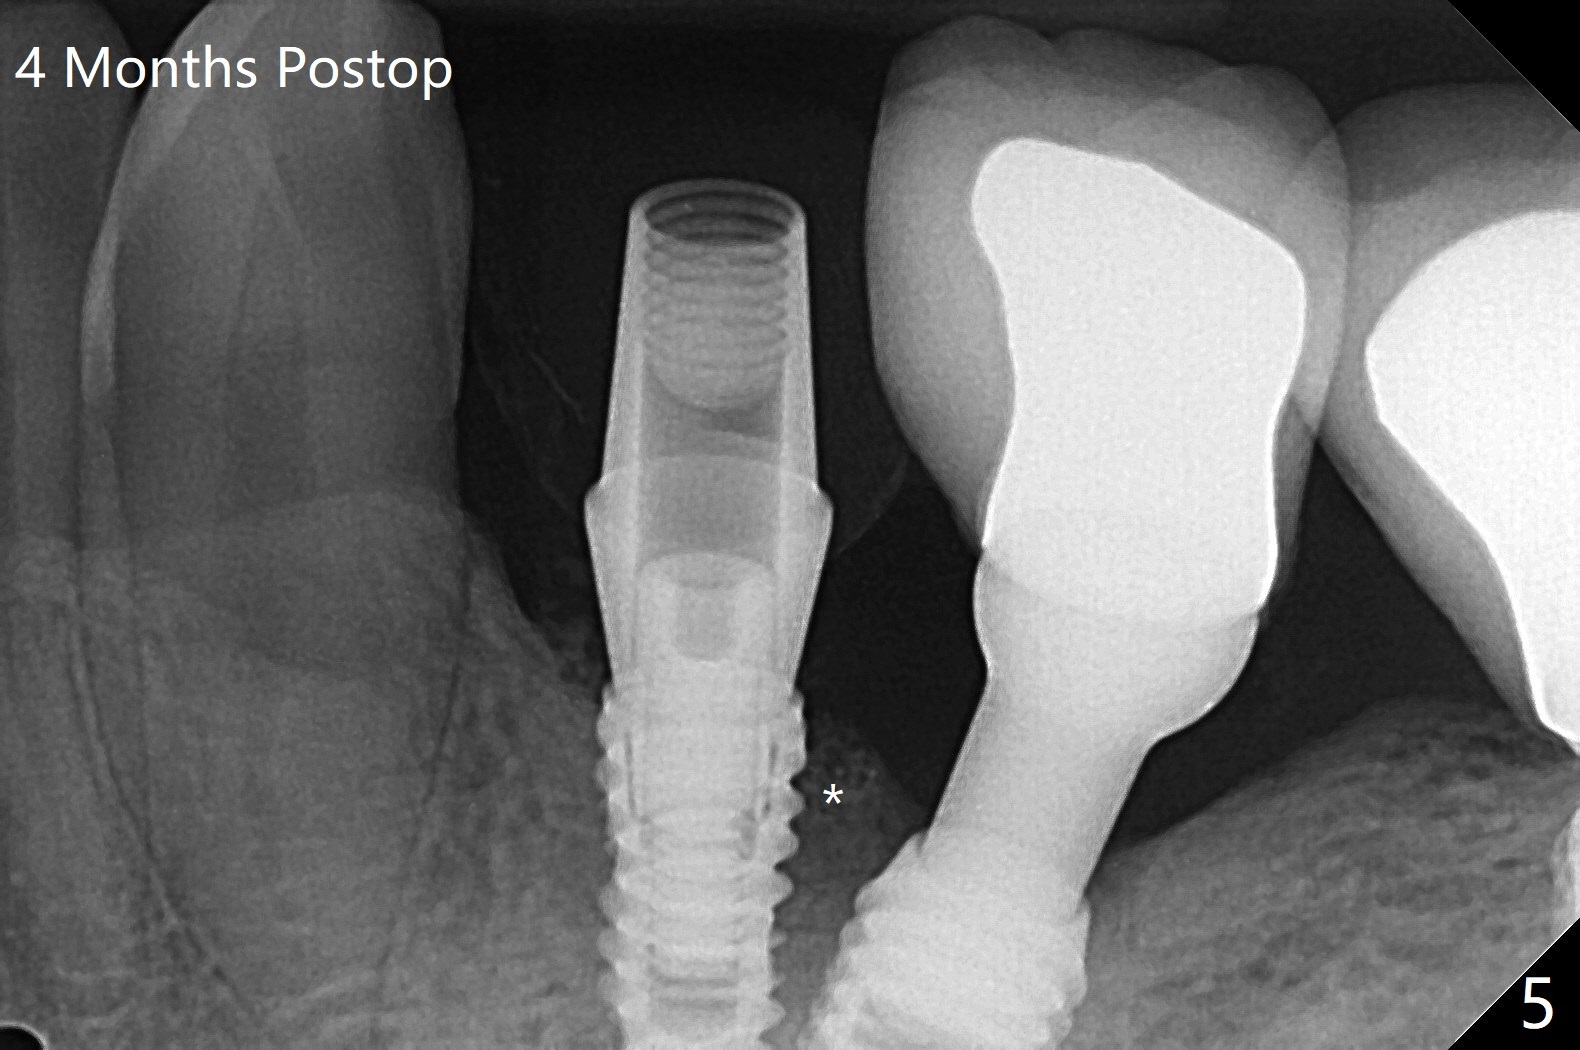

尽管使用导板,钻洞也不快,左下4植体仍旧偏移远中(图一)和颊侧(颊侧间隙比预计小),原因:斜面(图一:箭头),骨质硬,周围牙冠射线折射,导板就位前必须磨第二前磨牙近中面(今后遇到这些情景,选择徒手种植)。庆幸的是牙槽嵴水平两个植体还不是最接近(与根尖相比),粘性植骨(图一:*)但愿能缓解术后骨质吸收。制作临时牙冠后(图二:P),将PRF(图二:^;三:L(舌侧))插入牙冠和骨粉之间。术后六天软组织愈合正常(图四)。术后4个月远中牙槽嵴稍微下降(图五:*)。由于基台偏向远中,为了防止牙冠基台重新插入困难,基台不取出,先拧紧(20Ncm),牙冠口内粘固。